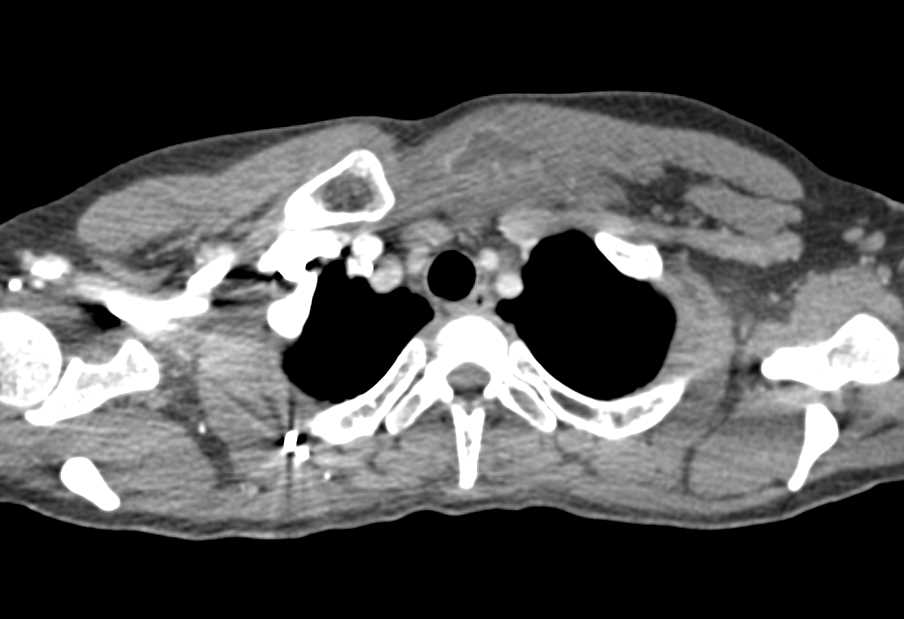

Thymic Hyperplasia